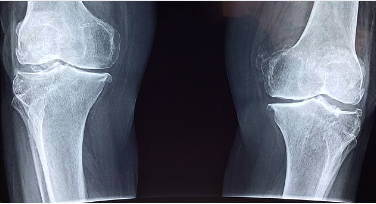

슬개골연골연화증의 진단

슬개골연골연화증은 다양한 진단 방법을 통해 확인할 수 있습니다:

영상 검사: X-ray나 MRI를 통해 슬개골과 주변 구조를 확인하여 슬개골연골연화증 여부를 판단합니다.